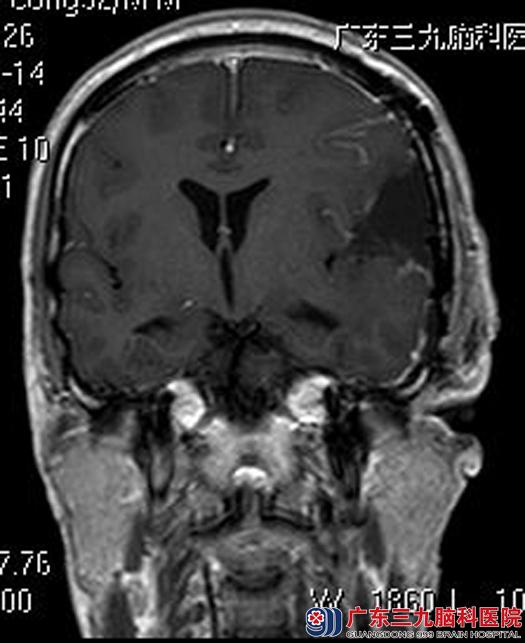

在亲属的陪同下,他们来到广东三九脑科医院。头颅MRI检查显示:左侧额颞部占位性病变,大小约6.9cm×3.9cm×6.2cm,考虑脑膜瘤。

由综合神经外科鲁明主任主刀,在全麻下行左侧额颞部脑膜瘤切除术,术中见肿瘤明显侵犯硬模,呈灰褐色,质中,血供丰富,在显微镜下将肿瘤全切。术后丘先生头痛症状明显好转,已康复出院。术后病理结果:过渡型脑膜瘤。